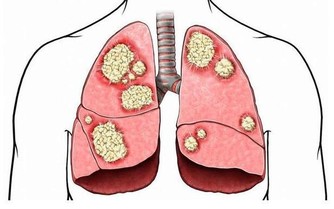

許多受傷的病人在一開始就有胸悶,尤其是那些長期不運動的病人,血管很容易出現血塊,血塊形成血栓,嚴重的危險是隨時可能脫落,血液流入肺部。

如果血栓較大或者較多,就會卡在肺動脈的分支或者主幹上,引發大面積的肺梗塞,出現胸悶、胸痛、咳嗽、呼吸受阻等不適,嚴重會危及生命。